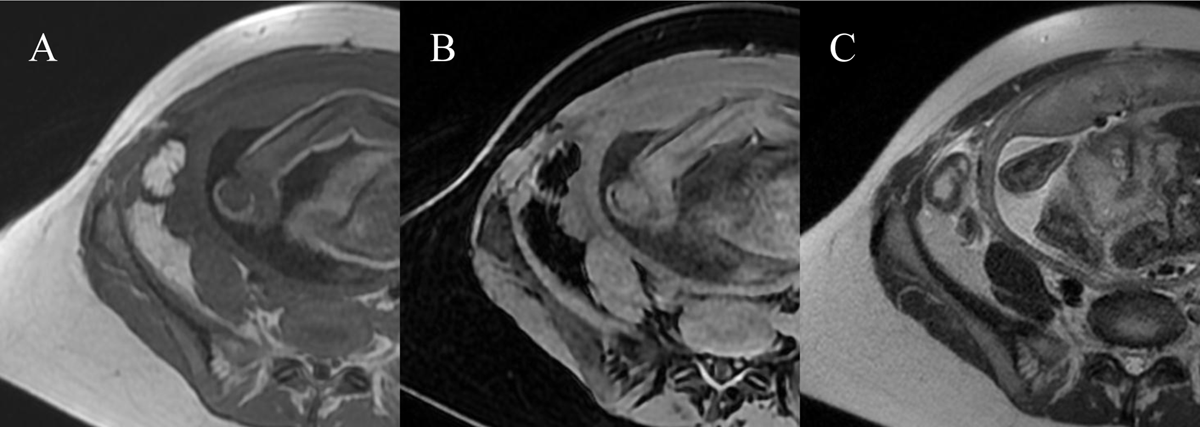

Figure 2

Right iliac fossa MRI. A) T1 sequence showed a anterior superficial intraperitoneal oblong mass in the right iliac fossa of 35mm hypersignal slightly less intense than normal fat with a thin peripheral hyposignal. B) T1FS sequence showed hyposignal of the mass with a fine periperal hypersignal. C) Hypersignal T2 of the mass and hypersignal T2 in the fat around.